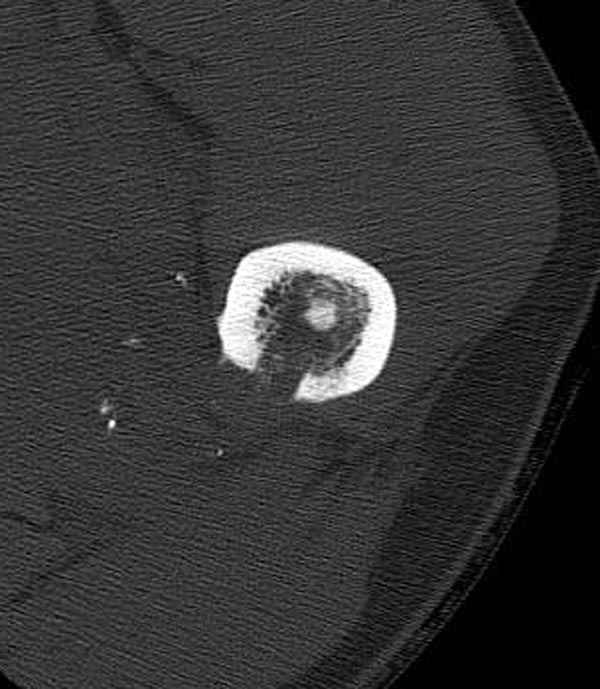

Больной с огнестрельным переломом бедра с вовлечением около 15% медиального кортекса, входное отверстие около 1 см в диаметре; стабильный, без сосудистых и неврологических признаков.

Литературные данные о влиянии кортикального дефекта на стрессовые переломы в длинных трубчатых костях в основном встречаются в онкологии, например кортикальный дефект более 50% имеет больше шанса стрессовых переломов, чем в нашем случае.

Учитывая, что больной получил травму не во время визита в церковь, и он является одним из представителем 40 миллионного “outstanding itizen”, без медицинской страховки, без работы в свои 39 лет, и без надлежающей ортопедической дисциплины у которого отсутсвует страх стрессового перелома, было рекомендовано оперативное лечение: профилактическое антеградное интрамедуллярное штифтование.

Методика штифтования при отсутствии большой зоны перелома как при онкологических профилактических штифтованиях, расверливание интрамедуллярного канала проводим с предварительным наложением дополнительного дренажного отверстия в дистальном отделе бедра (в данном случаи в канале оставили 6.5 мм канюлированный шуруп), иначе при создании давления в канале во время сверления имеется опасность эмболизации легочной артерии тромбом.